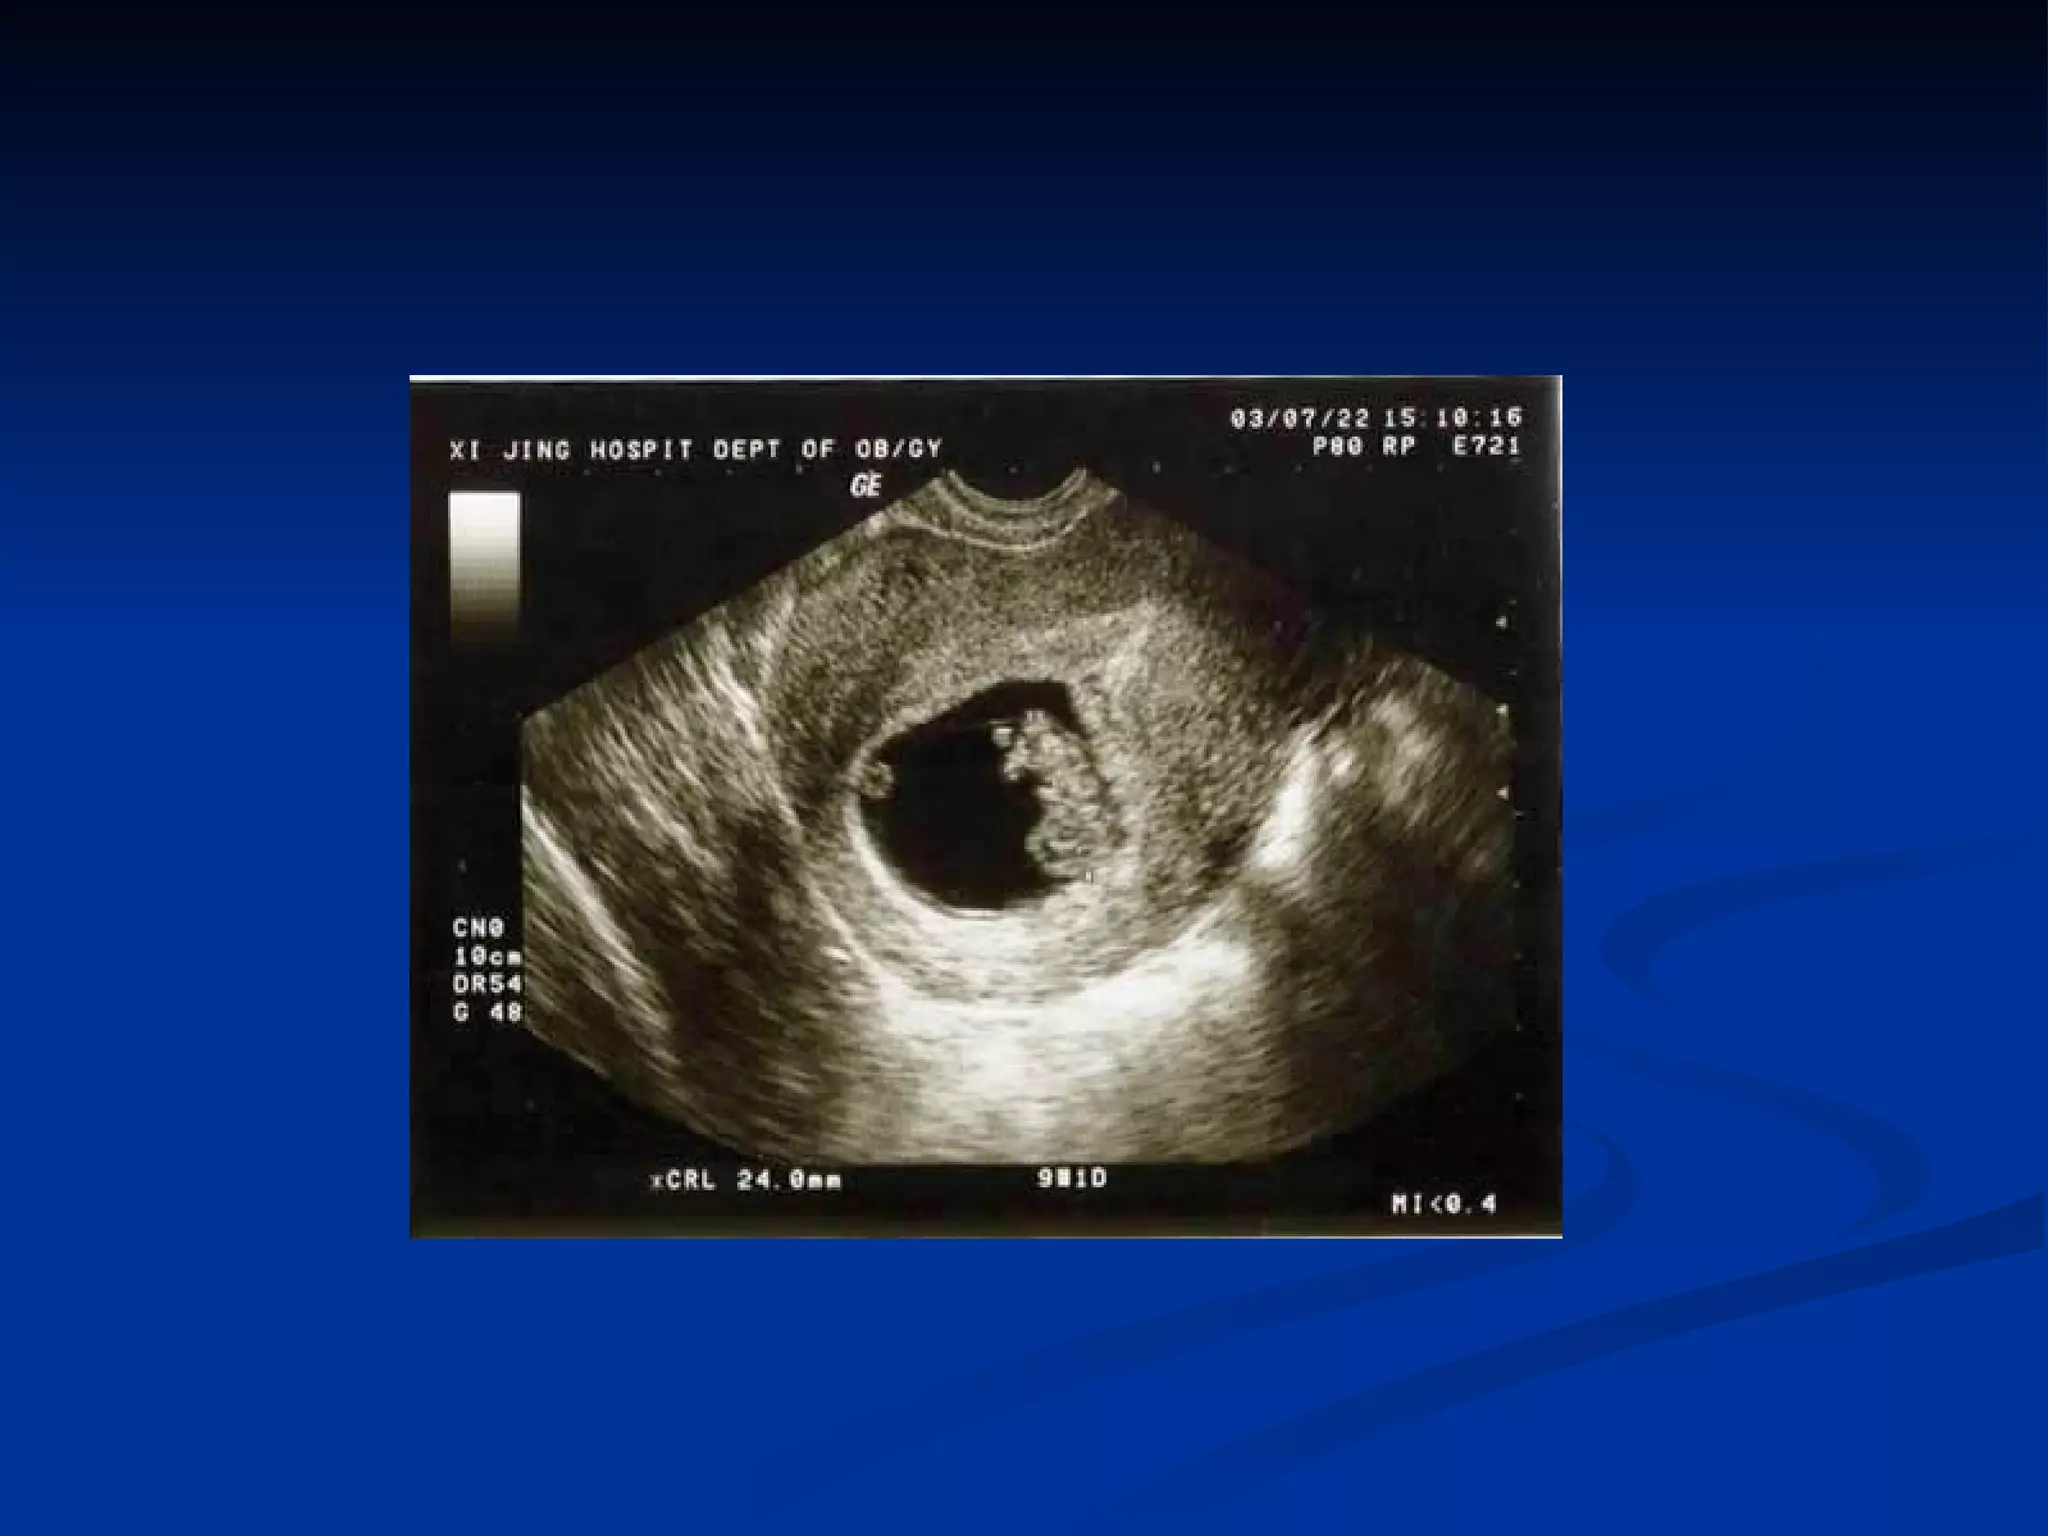

Ultrasonography This field has shown rapid technological improvements in recent years, and its application to the diagnosis of ectopic pregnancy, alone and in combination with hCG testing, is now the standard of care. Transvaginal ultrasonography has allowed the detection of an intrauterine gestational sac at as early as 5 weeks of amenorrhea (2 mm diameter).

If the sac is not visualized at the uterine cavity, special attention is needed to differentiate between a true sac and a pseudosac, which is a ring-like structure produced on ultrasound by a prominent decidual echo. Evidence of hemoperitoneum may be inferred by the sonographic description of “free fluid in the cul-de-sac.”